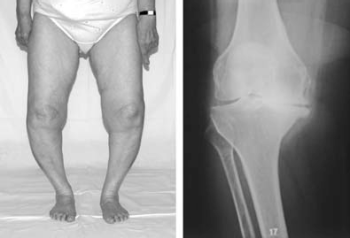

55.1.1. Arthrosis genus